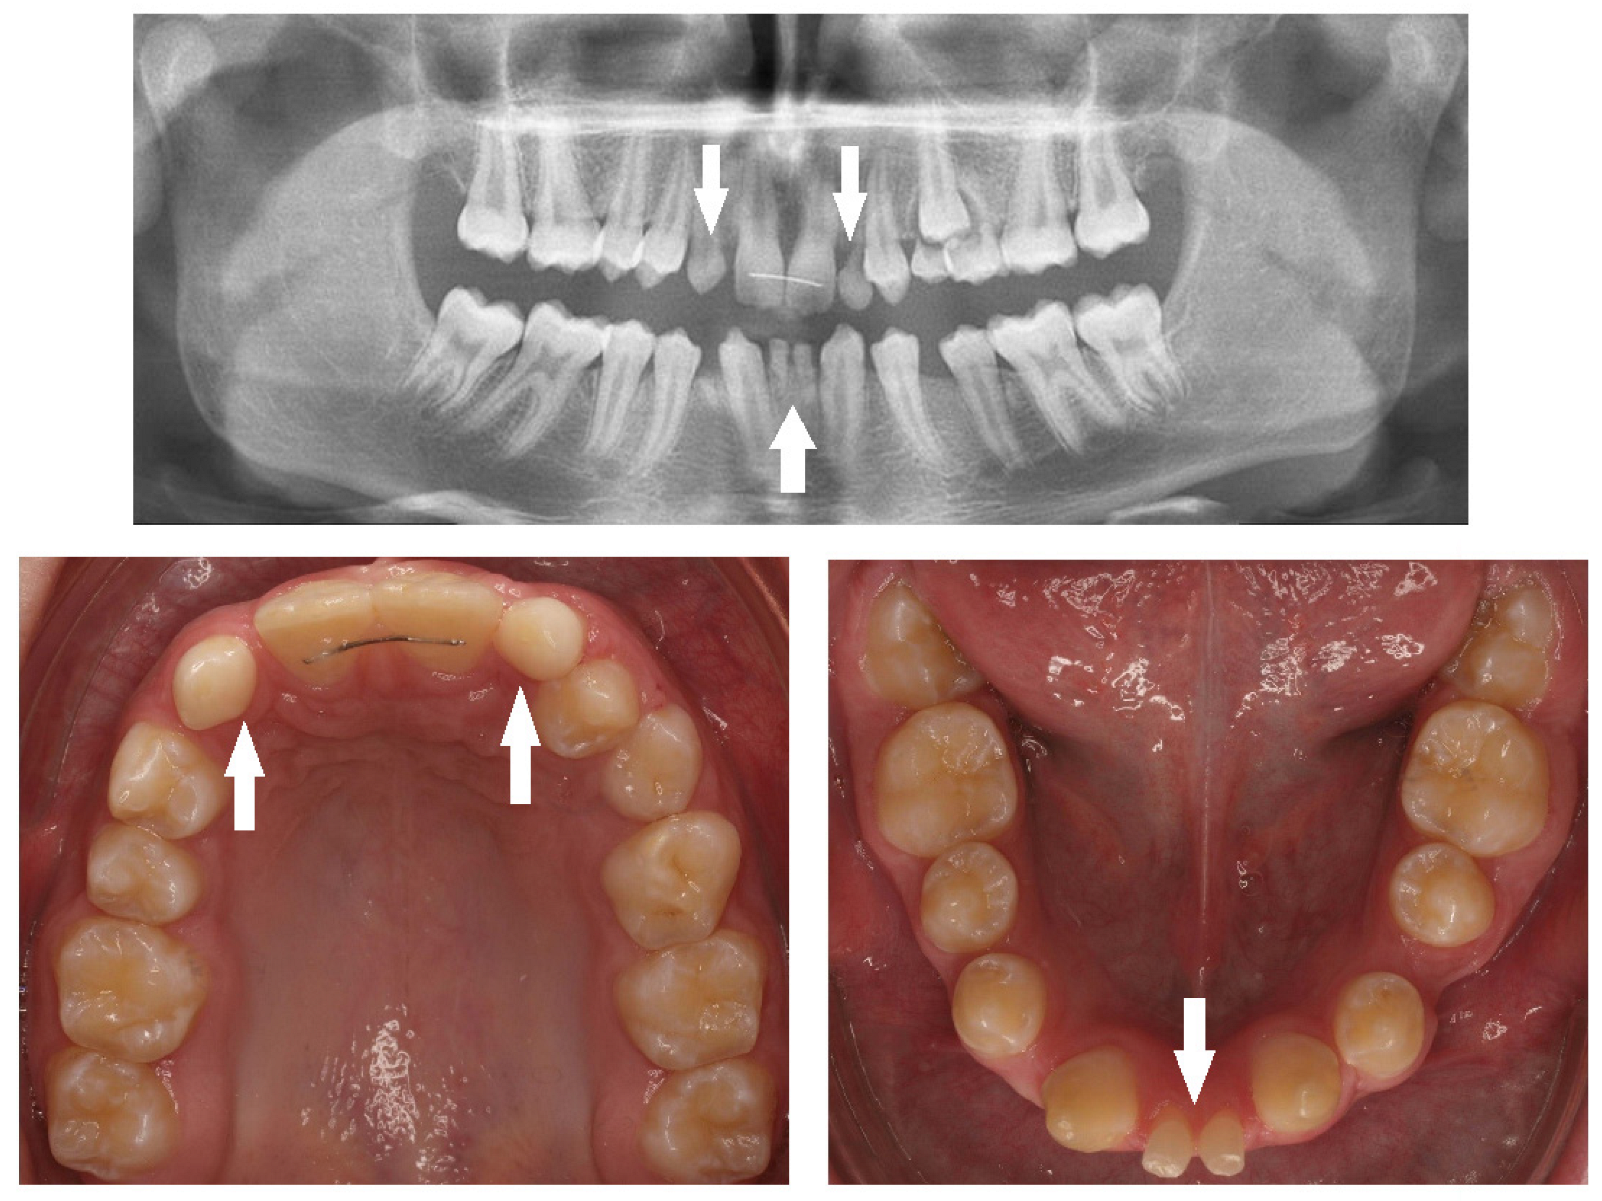

| Missing | Congenital absence of permanent teeth. |

| Impaction | Failure of tooth eruption into the oral cavity. |